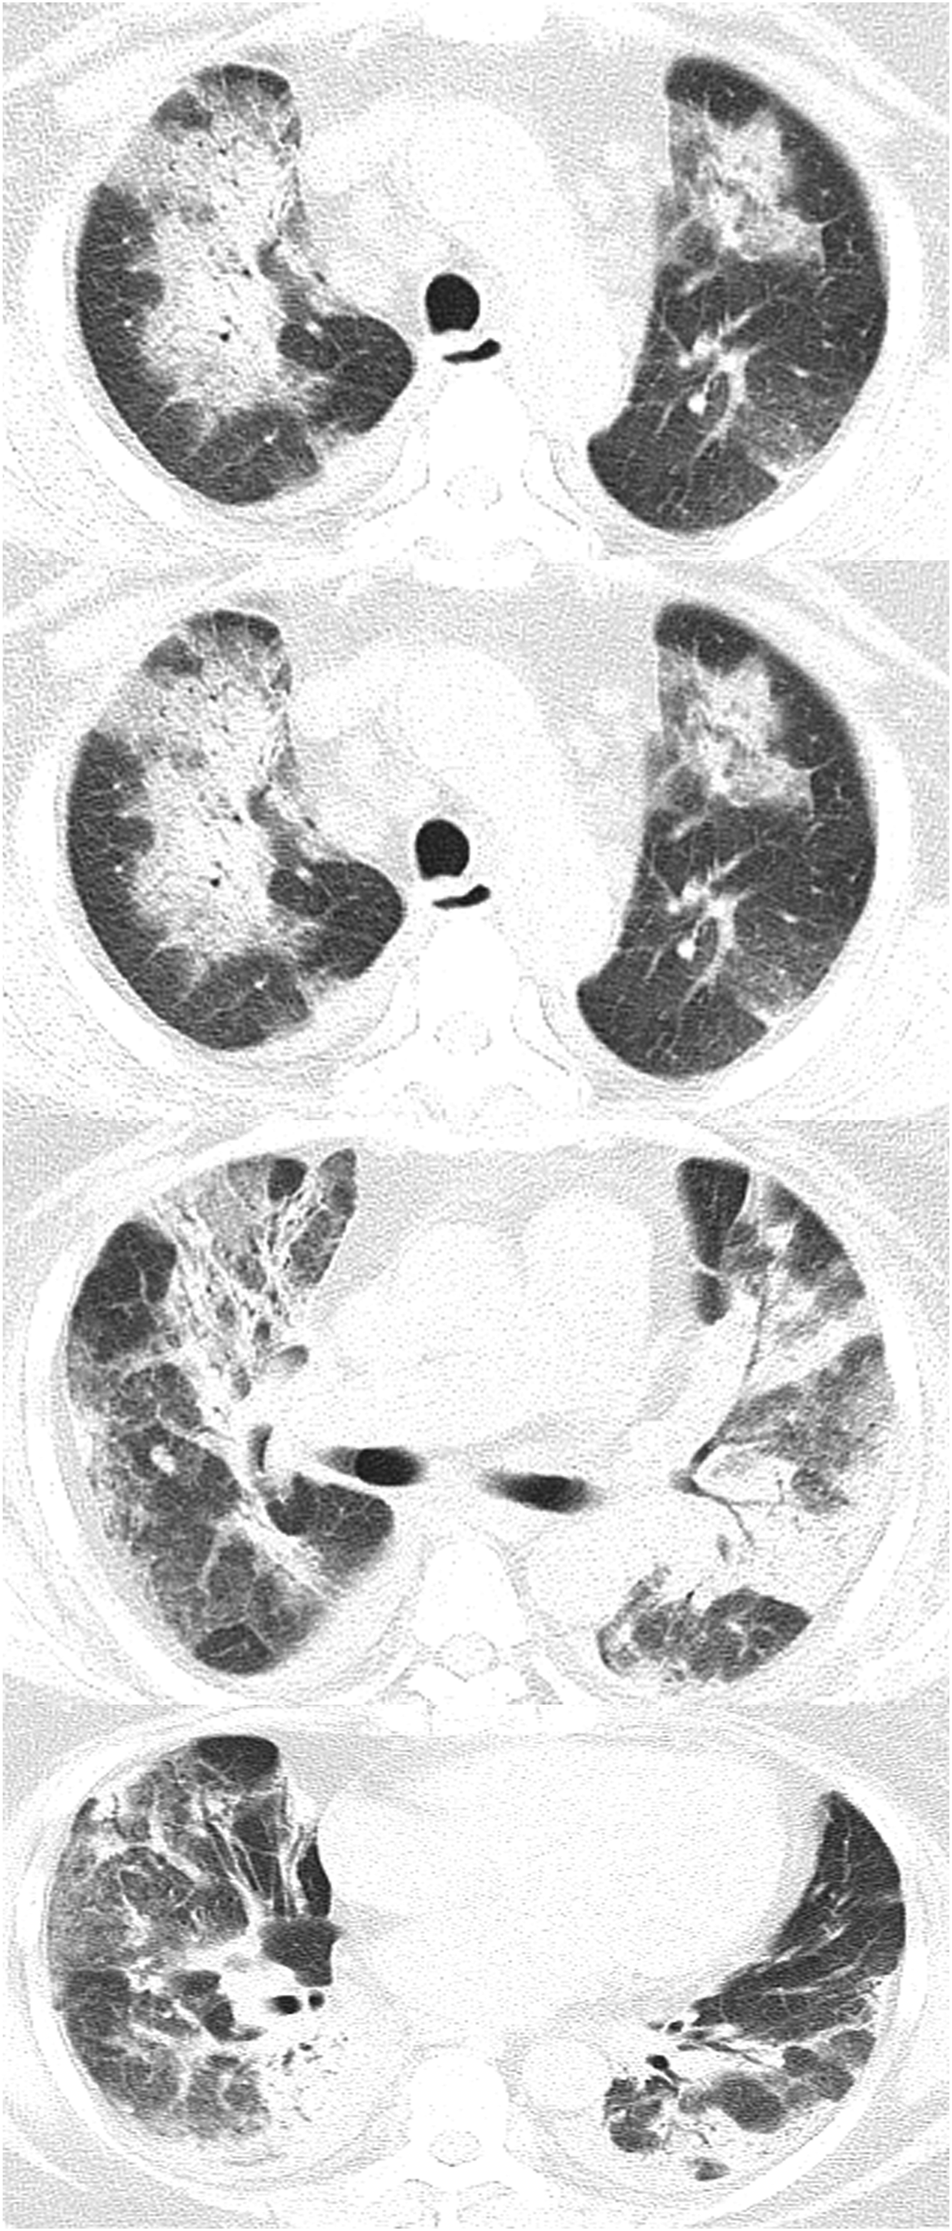

Chest Radiography and the Relationships Between Patient Characteristics and the CT Score

Chest radiography showed the presence of GGOs, traction bronchiectasis and consolidation (Figure 2). Radiologic changes included the lower line of the pleura and isolated areas of pleural thickening at 3°months. At 6°months after discharge from the hospital, all but 4 patients showed improvement on chest CT. The CT score improved dramatically during the 6°months, and the difference was statistically significant (P < 0.05) (Table 1).

FIGURE 2

www.frontiersin.org

FIGURE 2. These scans are of a 64°year-old woman with an H1N1 infection confirmed by a sputum test. Chest CT scan demonstrates patchy shadows and ground-glass opacities in both lungs, with traction bronchiectasis and pleural thickening.